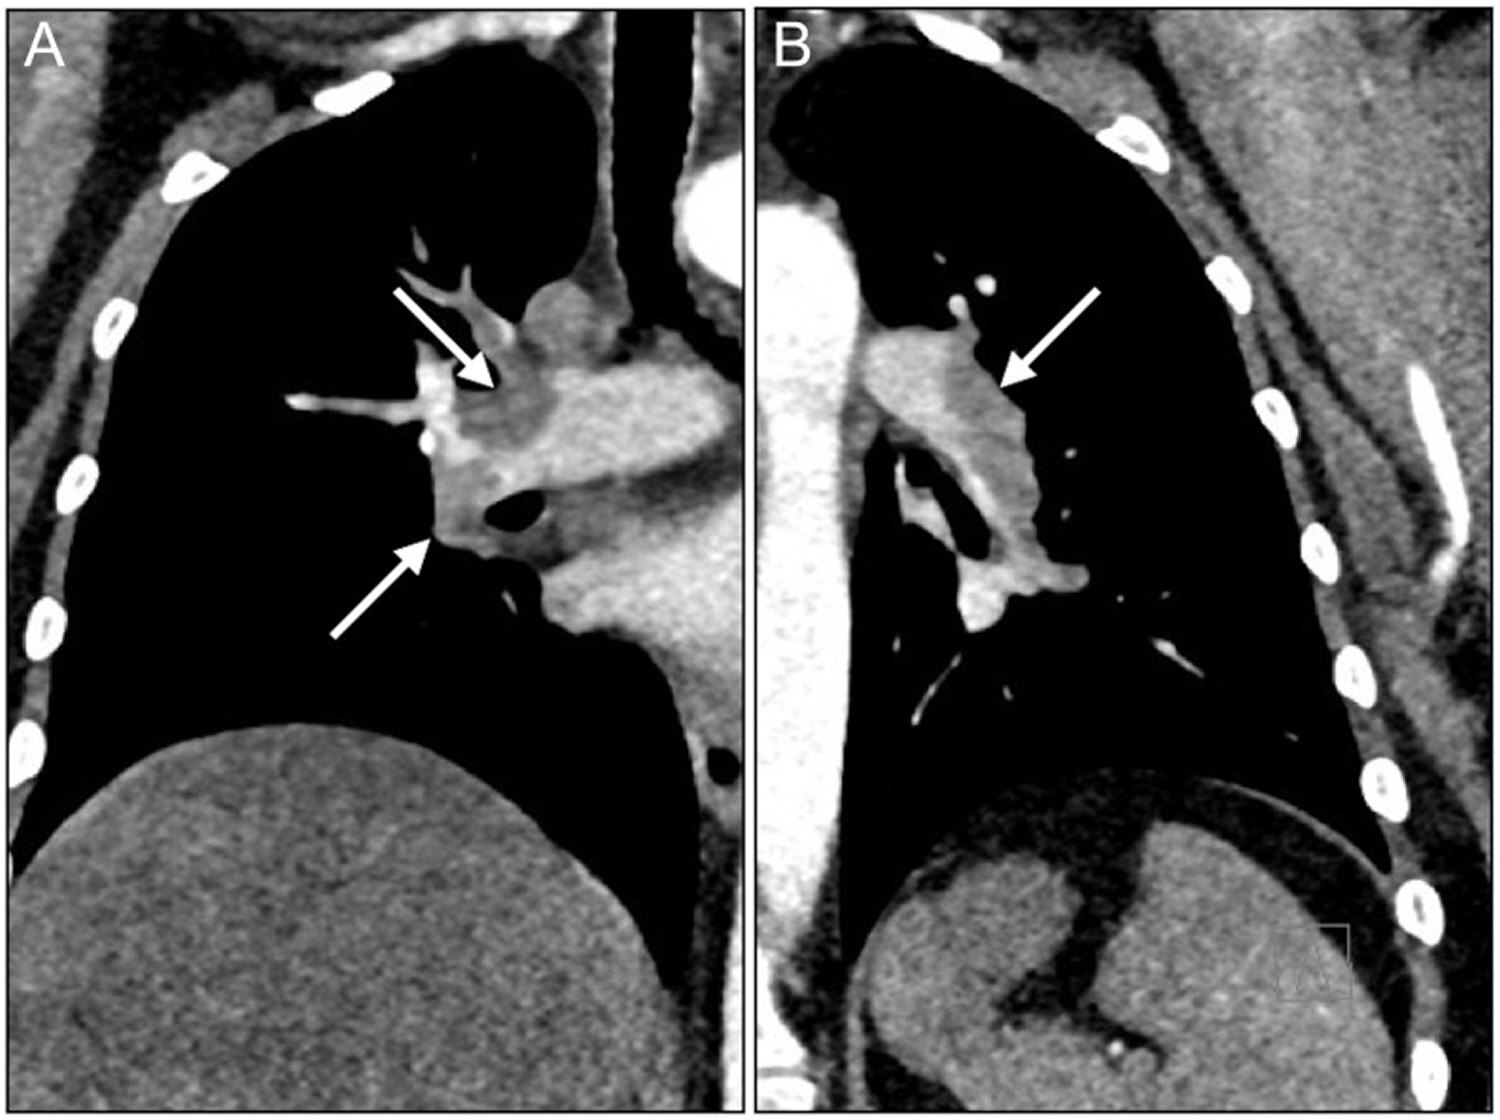

這天傍晚,醫(yī)生在門(mén)診診室看病。已經(jīng)比較晚了。具體時(shí)間就不說(shuō)了,反正比較晚了。天色,肯定是黑了,晚飯時(shí)間已經(jīng)是過(guò)了好一會(huì)了。是一個(gè)上了一天班的人,內(nèi)心深處歸心似箭想要下班回家的時(shí)間了,多一分鐘都是堅(jiān)持的這樣一個(gè)時(shí)間段。這時(shí),還剩下幾位等待的患者沒(méi)有就診。就在這個(gè)時(shí)候,診室叫號(hào),進(jìn)來(lái)了一位患者。68歲女性,主訴是,胸悶氣短3天。她什么初步檢查也沒(méi)有做、也沒(méi)有帶來(lái),就是平時(shí)身體都挺好的,最近原因不明的胸悶氣短了3天,她覺(jué)得憋不住了,下午臨時(shí)起意,只身一個(gè)人直奔醫(yī)院的心內(nèi)科門(mén)診而來(lái)。這其實(shí)是很常見(jiàn)的患者到門(mén)診就診的一個(gè)臨床場(chǎng)景,就是:看起來(lái),并不是有備而來(lái),就是在一個(gè)特定的時(shí)刻,在思想上,像是有一個(gè)壓倒駱駝的最后一根稻草,讓患者終于下定了去醫(yī)院的決心。患者的狀態(tài),也不是很差,不是那種一看就是要死要活的情況,否則,就會(huì)直接去急診看病了。顯然,這位患者也是這樣。只是,她下午來(lái)掛號(hào),輪到她看病的時(shí)候,已經(jīng)等了好幾個(gè)小時(shí)了,就到了前面所述的“天色都黑了、門(mén)診醫(yī)生的內(nèi)心深處歸心似箭的時(shí)間段。其實(shí),可以推測(cè),此刻的患者,也想早一點(diǎn)結(jié)束看病、早一點(diǎn)回家了,如果醫(yī)生覺(jué)得情況沒(méi)啥,開(kāi)些擇期的檢查讓她先回家以后再來(lái)完成,她肯定也是樂(lè)意的。如果用足球比賽來(lái)形容,那就是90分鐘踢完,再踢加時(shí)賽。30分鐘的加時(shí)賽又過(guò)去了25分鐘,就剩下最后幾分鐘了。兩方的球員,體力都快支撐不住,只想早點(diǎn)結(jié)束比賽了。這個(gè)時(shí)候,有經(jīng)驗(yàn)的球員懂得,絕殺翻盤(pán)的時(shí)機(jī),到了。那么,再回到天黑時(shí)段的心內(nèi)科門(mén)診診室。再看完這幾個(gè)病人,醫(yī)生就可以回家休息了??赐赆t(yī)生,患者就可能回家休息了。醫(yī)生測(cè)了測(cè)患者的血壓,正常,聽(tīng)診心率120,偏快,節(jié)律整齊,其它方面并無(wú)明顯陽(yáng)性體征。有經(jīng)驗(yàn)的醫(yī)生,一邊內(nèi)心里歸心似箭,一邊提醒自己,絕殺的時(shí)候,可能到了。疾病的診斷,就像是破案。壞人的臉上不可能寫(xiě)著“壞人”。患者疾病的正確診斷,不可能自己跳出來(lái)。是絕殺一個(gè)疾?。ò讶菀妆缓雎缘臐撛谖kU(xiǎn)性疾病正確及時(shí)地識(shí)別出來(lái)),還是被一個(gè)疾病絕殺(漏診,導(dǎo)致嚴(yán)重后果)?在這個(gè)即將結(jié)束一天的工作的準(zhǔn)下班時(shí)間段,很關(guān)鍵,很重要。于是,醫(yī)生并沒(méi)有因?yàn)樘焐诹?,患者也沒(méi)有提供任何檢查結(jié)果,就簡(jiǎn)單地開(kāi)出第二天的輔助檢查和化驗(yàn)單,就把她打發(fā)走,因?yàn)槟菢拥脑?,診斷的確認(rèn),最快也將是第二天的事情了。而有些疾病的診斷,卻是要越快越好,一旦錯(cuò)過(guò),也許是永遠(yuǎn)。于是,醫(yī)生耐住性子問(wèn),你這次來(lái)看病,什么檢查結(jié)果都沒(méi)有,那你以前做過(guò)心電圖或者心臟彩超嗎?;颊撸阂郧白鲞^(guò)心電圖、心臟彩超,都是好的,心臟彩超是去年在別的醫(yī)院做的。醫(yī)生問(wèn):你這次沒(méi)有胸痛吧?;颊撸簺](méi)有,就是氣喘,一活動(dòng)就喘,就心慌,心跳一百多。醫(yī)生注意到,患者一直戴著口罩,每說(shuō)完一句長(zhǎng)話,就會(huì)有上氣不接下氣的感覺(jué)。此時(shí),醫(yī)生的腦海里,已經(jīng)浮現(xiàn)出了一個(gè)疾病的診斷。醫(yī)生又問(wèn),你在家里,有沒(méi)有自己測(cè)過(guò)那個(gè)夾在手指頭的指脈氧?患者回答,測(cè)過(guò),只有百分之九十,最高也只有百分之九十四,以前從來(lái)沒(méi)有這么低過(guò)。至此,雖然只是簡(jiǎn)單地三言?xún)烧Z(yǔ)地問(wèn)診,醫(yī)生腦海里已基本確認(rèn)了最可能的疾病診斷,這是個(gè)有潛在的致命風(fēng)險(xiǎn)的疾病。醫(yī)生認(rèn)真地對(duì)患者強(qiáng)調(diào),雖然限于時(shí)間已晚,門(mén)診暫時(shí)不能馬上做相關(guān)檢查,但根據(jù)目前所了解的情況,高度懷疑你有了血栓性的疾病,也就是“肺動(dòng)脈栓塞”,建議你立即去幾十米外的急診科就診,做一系列的檢查,我把所有需要盡快完成的檢查項(xiàng)目,都給你寫(xiě)在病史冊(cè)上,你一定要馬上去急診查,幾個(gè)小時(shí)就可以完成這些檢查,相關(guān)結(jié)果報(bào)告出來(lái)后,再進(jìn)一步評(píng)估,才能決定你今晚是可以回家,還是留院繼續(xù)觀察治療?;颊呖吹结t(yī)生鄭重其事的樣子,認(rèn)真地采納了建議。隨后,患者在急診科完成了一系列檢查:D-二聚體高達(dá)16.11mg/L(較正常參考值超標(biāo)了幾十倍),肺動(dòng)脈增強(qiáng)CTA“兩肺動(dòng)脈分支多發(fā)栓子”,印證了門(mén)診醫(yī)生的診斷思路是正確的,的確是“肺動(dòng)脈栓塞”。有了正確及時(shí)的診斷,相信后續(xù)的進(jìn)一步檢查和治療,就容易得多了。這次,醫(yī)生絕殺了疾病。憑著經(jīng)驗(yàn),知識(shí),責(zé)任心。關(guān)于肺動(dòng)脈栓塞的相關(guān)知識(shí),以下內(nèi)容來(lái)自于AI的回答肺動(dòng)脈栓塞是一類(lèi)危險(xiǎn)性較高的疾病。原因有病情進(jìn)展迅速:肺動(dòng)脈栓塞是由于內(nèi)源性或外源性栓子堵塞肺動(dòng)脈主干或分支引起肺循環(huán)障礙的臨床和病理生理綜合征。當(dāng)肺動(dòng)脈被堵塞后,會(huì)導(dǎo)致肺組織的血液灌注減少,進(jìn)而影響氧氣交換。如果堵塞的血管較大,或者多個(gè)血管同時(shí)被堵塞,會(huì)在短時(shí)間內(nèi)引起嚴(yán)重的呼吸循環(huán)衰竭,患者可迅速出現(xiàn)呼吸困難、胸痛、咯血、暈厥等癥狀,甚至在數(shù)小時(shí)內(nèi)死亡。易引發(fā)并發(fā)癥:肺動(dòng)脈栓塞還可能導(dǎo)致一些嚴(yán)重的并發(fā)癥,如急性肺心病、心力衰竭等。這些并發(fā)癥會(huì)進(jìn)一步加重患者的病情,增加治療的難度和死亡風(fēng)險(xiǎn)。存在誤診漏診可能:如前面所說(shuō),肺動(dòng)脈栓塞的癥狀缺乏特異性,與其他一些心肺疾病的癥狀相似,容易被誤診或漏診。如果不能及時(shí)明確診斷并進(jìn)行有效的治療,患者的病情會(huì)持續(xù)惡化,危及生命。2021?年,中國(guó)肺栓塞新發(fā)患者數(shù)量超過(guò)?20?萬(wàn),人群發(fā)病率高達(dá)?14.19/10?萬(wàn)人。肺血栓栓塞是最常見(jiàn)的急性肺栓塞類(lèi)型,由來(lái)自靜脈系統(tǒng)或右心的血栓阻塞肺動(dòng)脈或其分支所致。國(guó)內(nèi)雖然沒(méi)有近年確切的肺血栓栓塞漏診率統(tǒng)計(jì)數(shù)據(jù),但過(guò)去國(guó)內(nèi)外尸檢報(bào)告顯示,肺動(dòng)脈栓塞的誤、漏診率高達(dá)?67%-79%。這主要是因?yàn)獒t(yī)生對(duì)該病的認(rèn)識(shí)不足,其次是缺乏必要的診斷檢查手段,以及未能正確合理地應(yīng)用這些檢查手段。近年來(lái),隨著我國(guó)急性肺栓塞防治項(xiàng)目的開(kāi)展,臨床對(duì)該病的認(rèn)識(shí)不斷深入,檢出率有所提升,但由于其臨床表現(xiàn)無(wú)特異性,誤診和漏診的情況仍然可能存在。